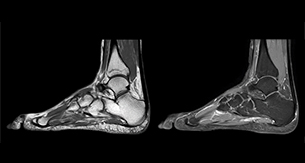

“In peripheral joints, mDIXON TSE imaging aids in diagnosing injuries in ligaments or tendons, for imaging degenerative and inflammatory pathologies such as osteoarthritis and rheumatologic disorders and for oncological exploration.”

“For tendon and ligament assessment around knee, ankle, hip and elbow, mDIXON TSE contributes to diagnostic confidence thanks to having images both with and without fat suppression – and without time penalty. This is possible because 2-point mDIXON is faster than the common 3-point Dixon method. It can also increase efficiency as it helps avoid having to add scans during the exam.”

“In peripheral joints, we get good image quality in difficult areas with mDIXON TSE.

Fat suppressed images appear homogeneous over the entire image, even with large coverage at 3.0T – for instance in scapular or hip girdles – or in the bearing areas or around metal prostheses, where fat suppression is often deficient with STIR or spectral fat suppression, causing diagnostic difficulties. If a diagnostic image is right the first time, we don’t need to repeat or add a sequence.”

“mDIXON TSE sequences allow simultaneous characterization of morphological changes from the in-phase T2-weighted images and visualization of edematous changes, thanks to the water T2-weighted images from the same acquisition. Anatomical and morphological considerations could be a partial or complete ligament tear, a bony avulsion or hematoma.”